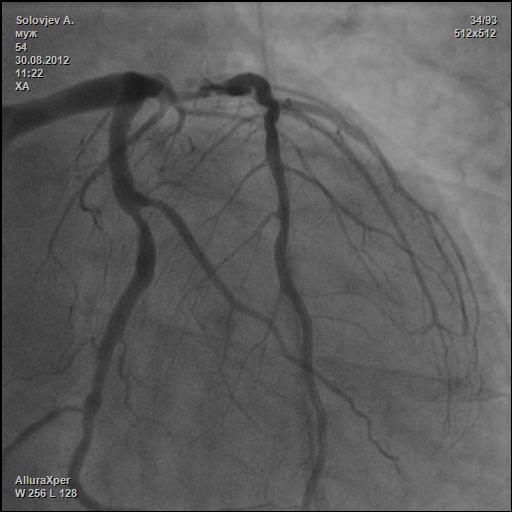

М. 54г. Ел пил все подряд. Лечили подагру, когда прижмет. Курил сигаретки. И вот тебе сюрприз.

Ваш диагноз? Как лечить?

frame_lst_0004.jpg

frame_lst_0004.jpg [ 27.28 KiB | Просмотров: 27907 ]

Конечно, нужно бы еще ангиограмм

АКШ